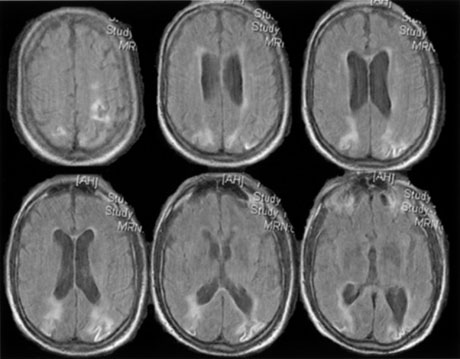

Cerebral blindness is distinguished from ocular disease by both normal pupillary light responses and normal fundoscopic examination. These may lead to an erroneous diagnosis of factitious visual loss. Associated signs of damage to parietal or temporal structures help to confirm cerebral blindness but may not always be present. Visual evoked potentials are of limited diagnostic value. They can be altered voluntarily by subjects without visual loss67 and can be normal in patients with striate lesions.68,69 They cannot differentiate between blind and seeing children with neurologic disease,70 and normal or abnormal results do not predict visual outcome.60,71 Absent evoked responses are rare and may only occur early in the course.70 Absent alpha rhythm on electroencephalography72,73 is reportedly a more sensitive diagnostic sign than abnormal visual evoked potentials.60 CT scans can be normal, but modern MR imaging with coronal images through the occipital lobe should reveal most striate or optic radiation lesions with complete and persistent visual loss (Fig. 16). Single photon emission computed tomography (SPECT) scans may reveal bilateral functional defects in cases with unilateral MRI lesions.74